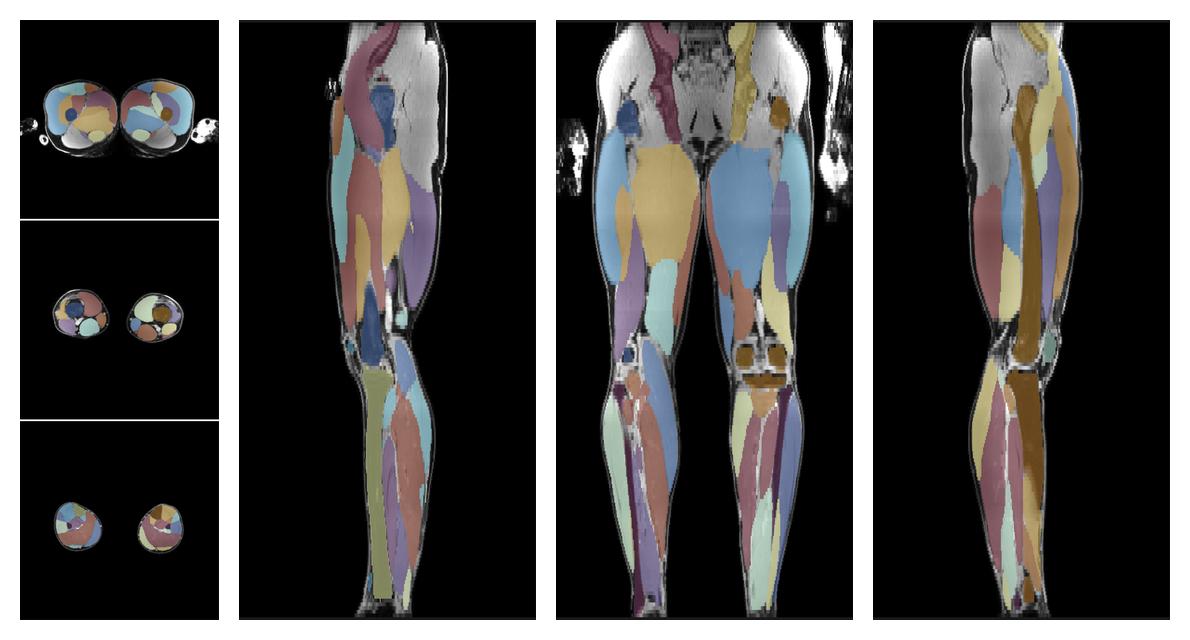

Muscle segmentation

Convolution neural network based (UNET) fiber automated muscle segmentation, for information look here».

• Automated muscle and bone segmentation.

Overlay of automated muscle segmentation labels on dixon water image.